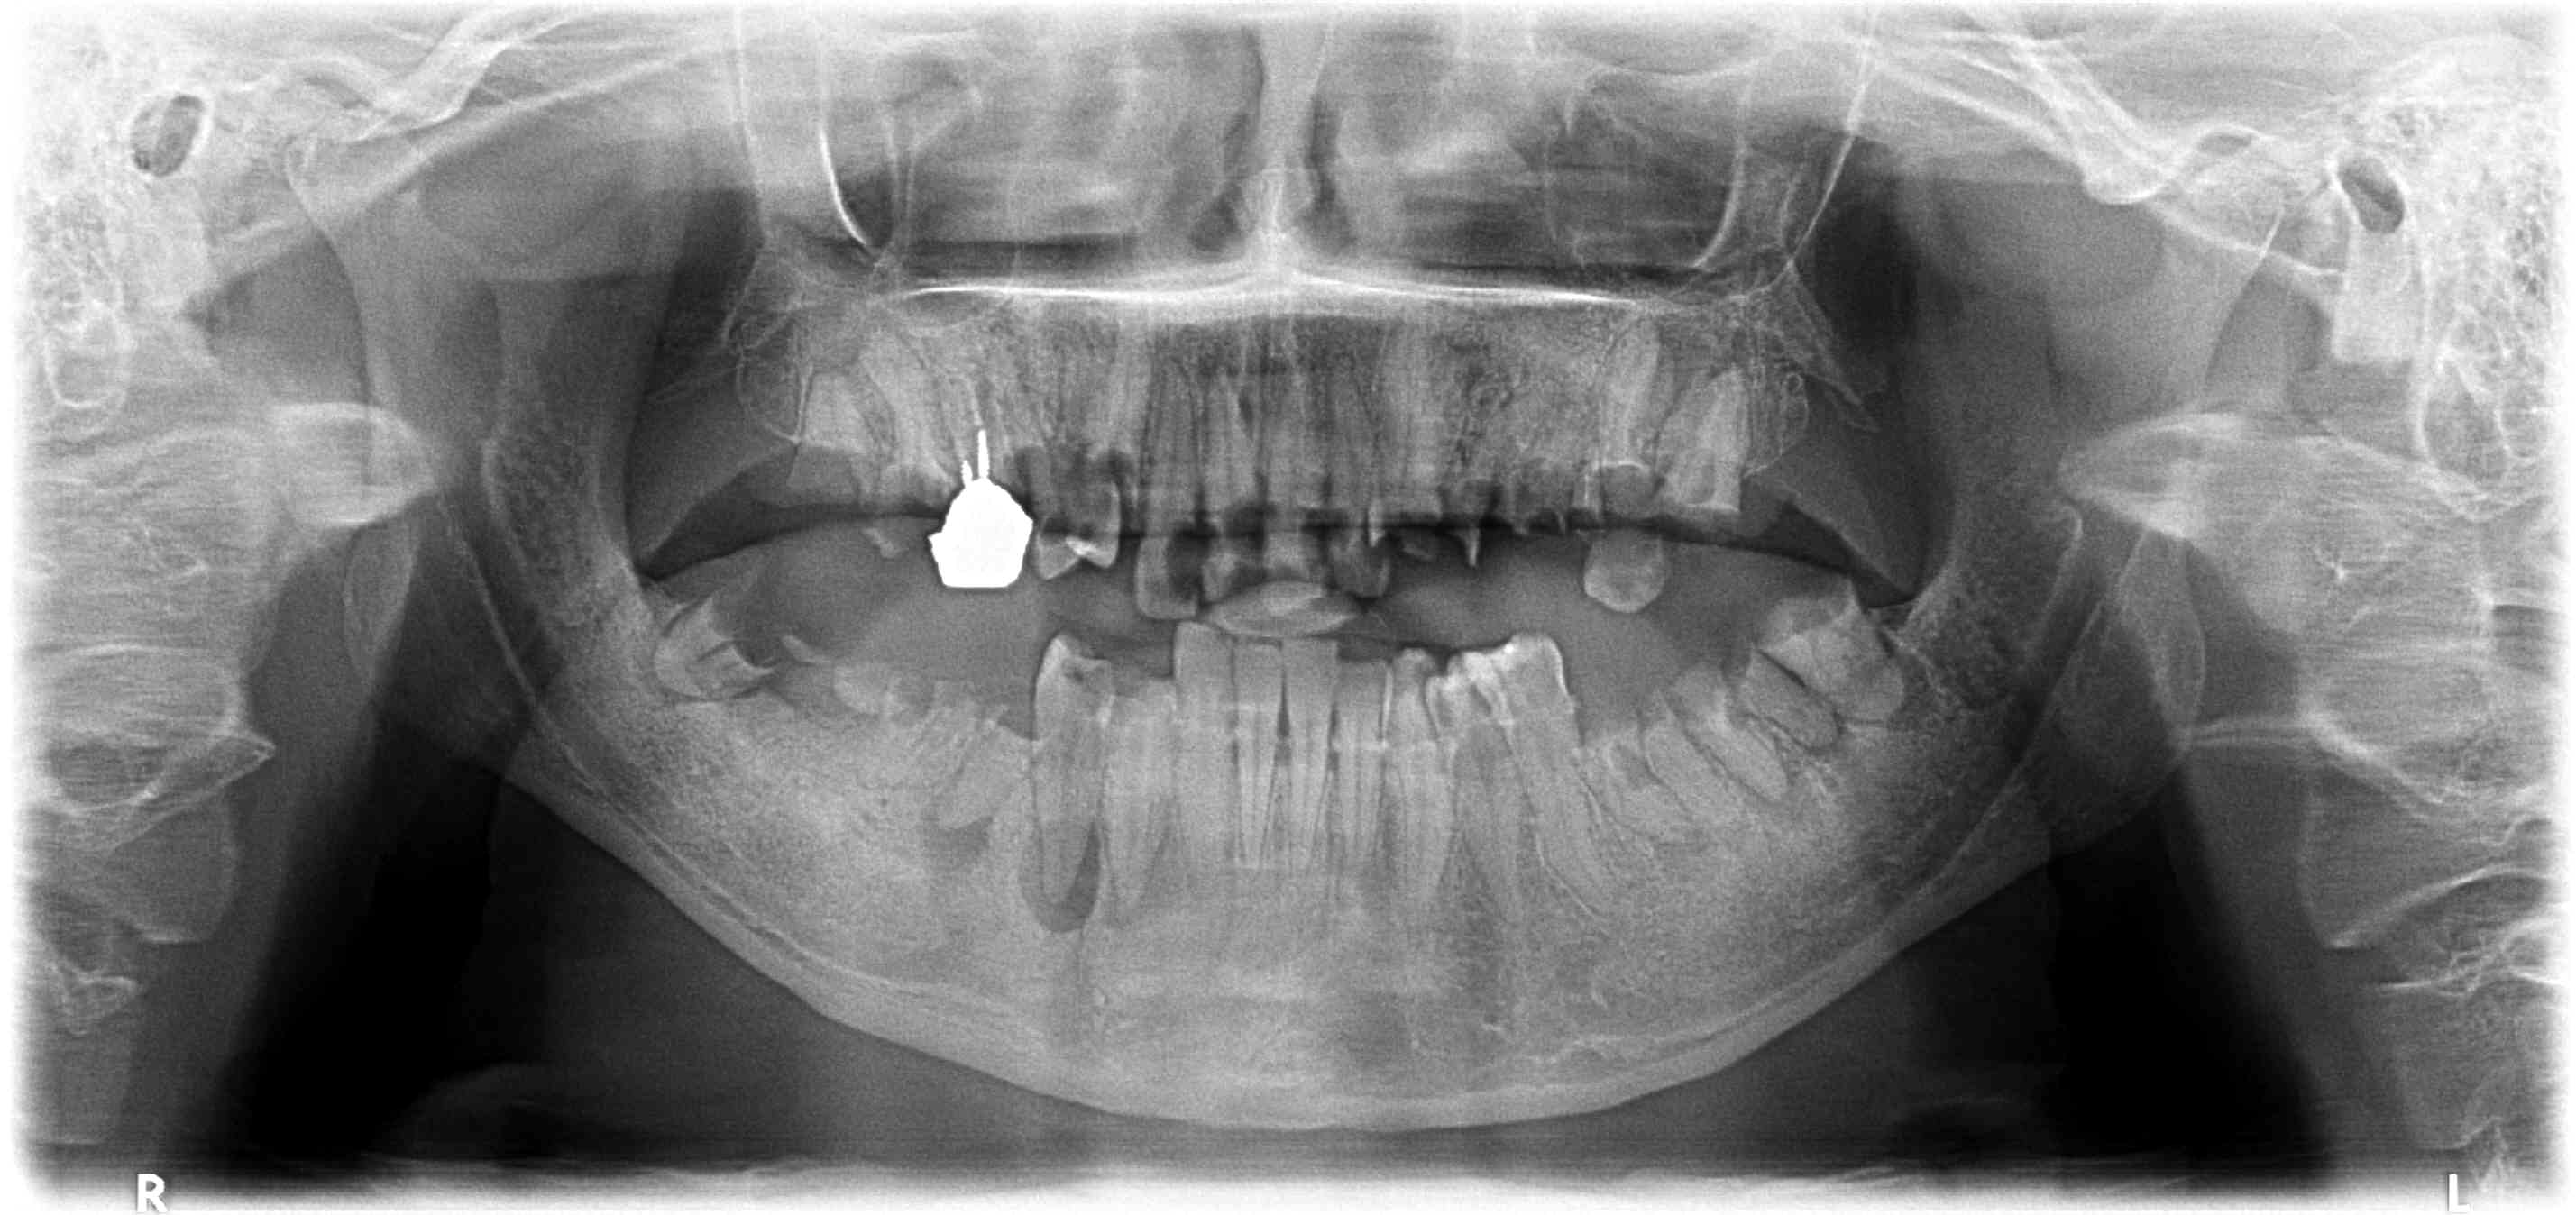

Capture d écran 2017 07 03 21.01 - Eugenol

chicot29

Et ca ca vaut quoi ?

Capture d écran 2017 07 03 21.08 - Eugenol